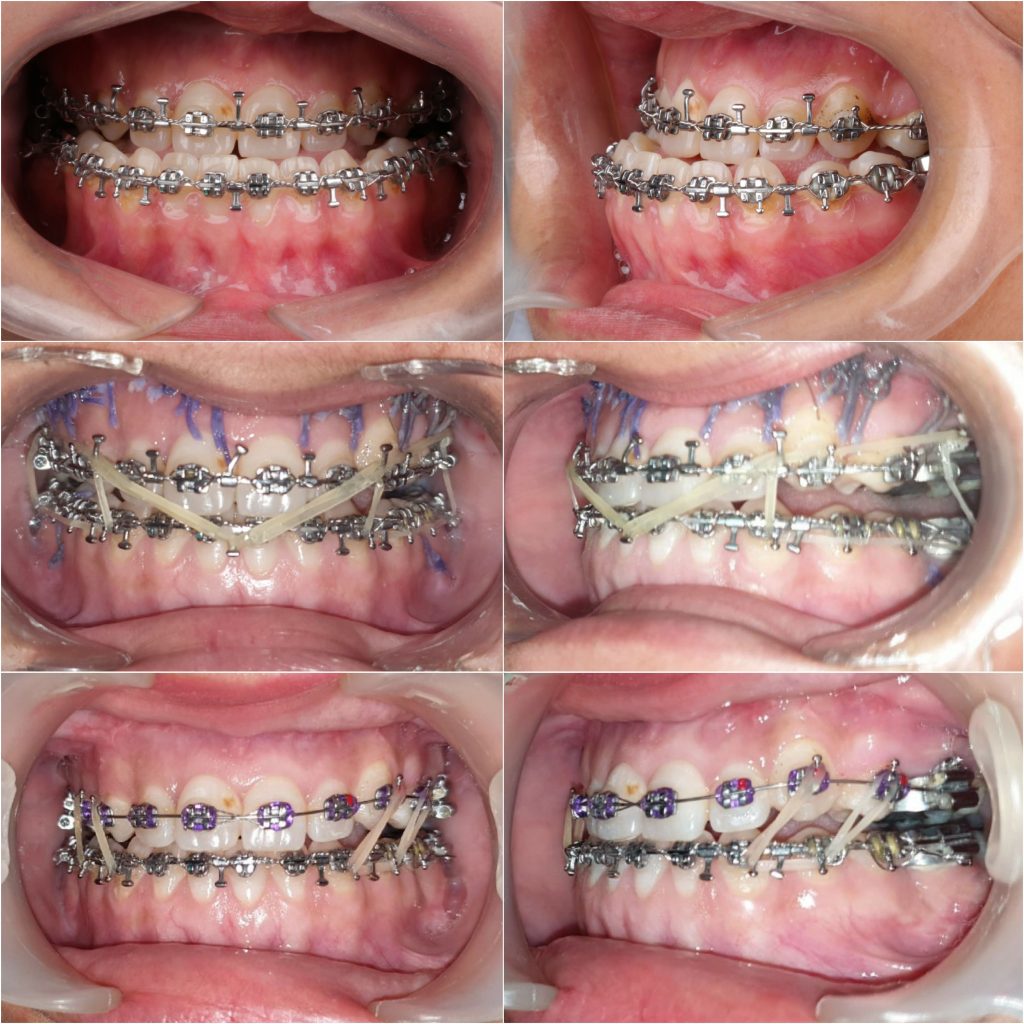

*Intraoral : incisors cl III complicated with sever crowding in upper arch , extracted UR3 , LR and LL 6s , anterior and posterior crossbite , upper midlineshift to the right , multiple restorations and fair OH

- A . Orthodontic preparation : including extraction of UL 4 , leveling and alignment , decompensation , arch coordination , creating surgical wafers for bimaxillary surgery and referred to the surgeon

* complication : the case dismissed after surgery without instructions to keep using the wafer along with elastics , also multiple debondings happened during the surgery , so patient came to me 3 weeks after surgery with posterior openbite , progressing shift of lower midline towards the right side , and cl III canines in left side

*managment : intermaxillary elastics , and unilateral buccal shelf TAD inserted in left side to distalize this segment to obtain cl I canine , and coincident midline .